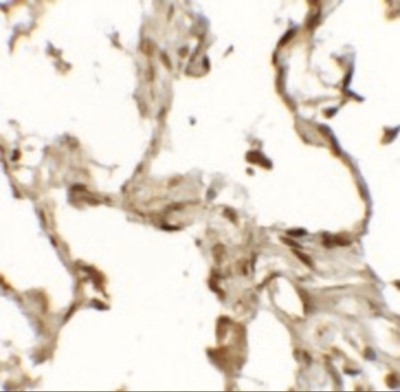

Supportive validation

- Submitted by

- Novus Biologicals (provider)

- Main image

- Experimental details

- Immunohistochemistry-Paraffin: TFEB Antibody [NBP2-41167] - Human lung tissue with TFEB (NT) antibody at 2.5 ug/mL.